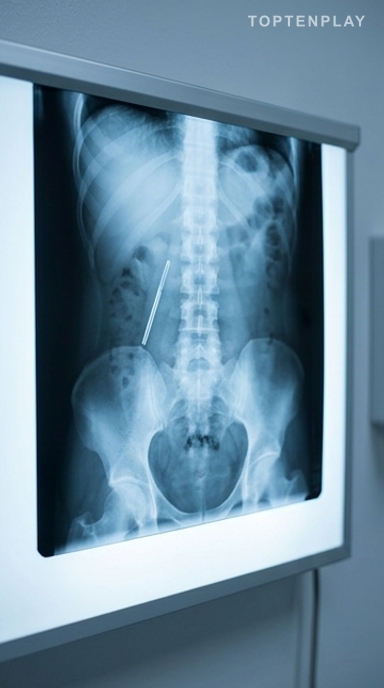

Un Chinois de 32 ans souffrant de douleurs abdominales a découvert, au printemps 2026, qu’un thermomètre à mercure avalé accidentellement à l’âge de douze ans était toujours logé dans son corps. Deux décennies de silence, aucun symptôme pendant la majeure partie de ce temps, puis une opération d’urgence de vingt minutes pour extraire l’objet intact. Ce cas, relayé par le South China Morning Post, révèle les dangers durables et méconnus de l’ingestion de corps étrangers.

Wang avait douze ans lorsqu’il avala accidentellement un thermomètre à mercure. Trop effrayé pour en parler à ses parents, il garda le secret. Les jours qui suivirent ne produisirent…